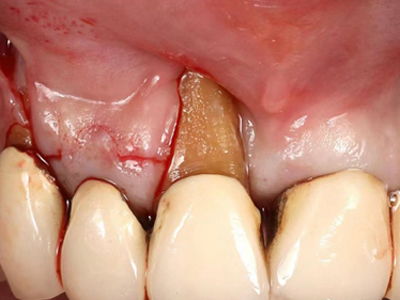

牙龈退缩多处牙龈萎缩出血图

牙龈退缩严重时,上排牙有多颗牙齿的牙龈部位发生退缩,导致牙根暴露,同时牙龈处还有出血的症状,伴有疼痛感,建议及时前往医院通过手术等手段进行治疗。